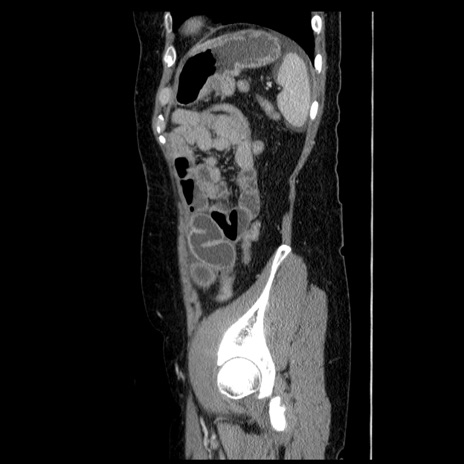

症例6(矢状断像)

【症例】50歳代女性

【主訴】下腹部痛

【現病歴】本日朝より下痢2回あり。 昼食を食べた後、嘔吐3回、下腹部痛認め、症状軽快せず、当院救急搬送。

最終食事:本日昼(生ものなし)。 昨日の夜、刺身を食ぺたとのこと。周囲に同様の症状の者なし。普段、排便は毎日あるとのこと。

【既往歴】卵巣癌術後(8年前に当院で卵巣摘出)

【身体所見】 意識清明、腹部:平坦、腸蠕動音→、やや硬、下腹部自発痛・圧痛あり、反跳痛あり、筋性防御なし。

【データ】WBC 16000、CRP 0.01